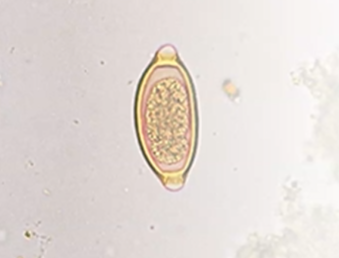

What is the species in this photo and WHY? Where is it found?

Schistosoma mansoni (has a VISIBLE lateral spine the pokey part) Stool